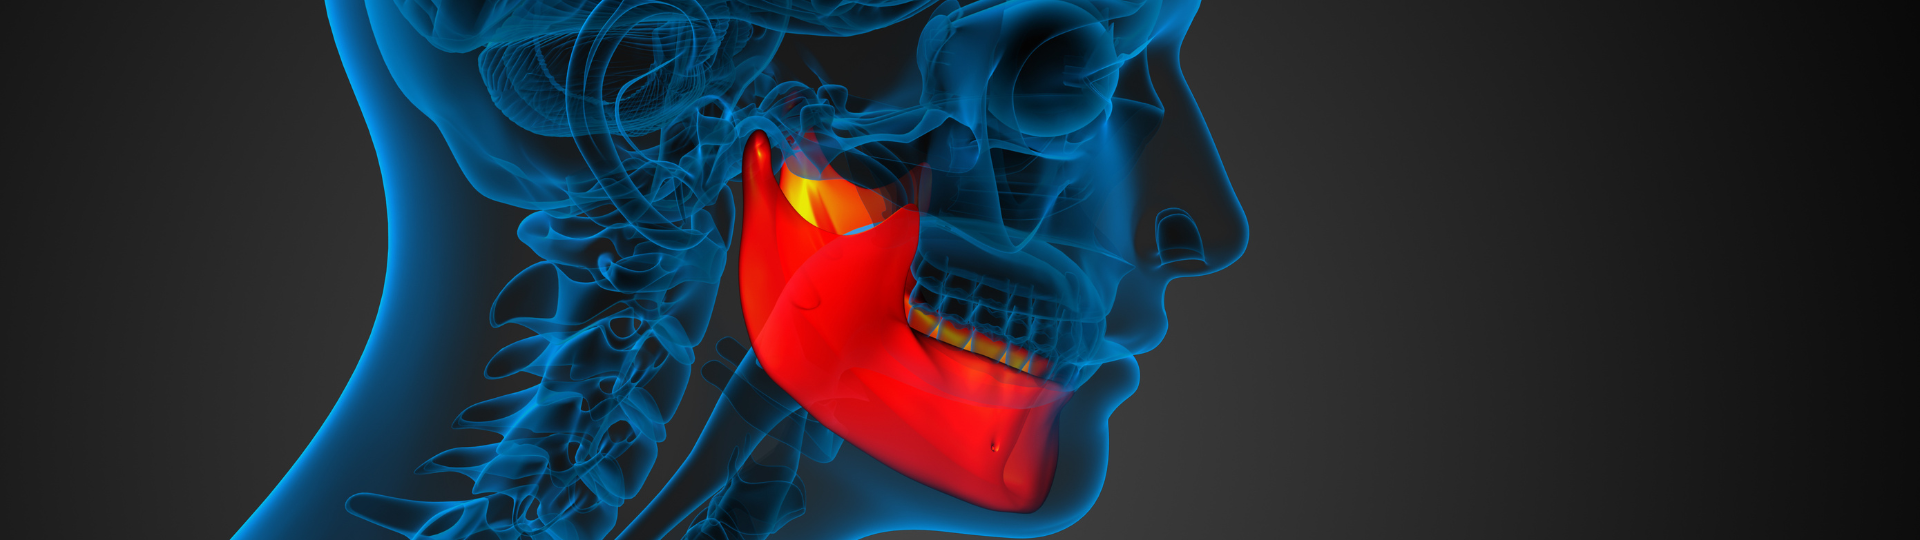

Il Dottor Eugenio Pecchioli, tutor del team medicale TQG, ha elaborato uno studio sull’utilizzo dell’elettrodo endorale con Velvet TMJ. Il dispositivo Top Quality Health è una tecnologia distrettuale non invasiva a Diatermia Capacitiva e Resistiva ed Elettroporazione, utilizzabile nella pratica quotidiana odontoiatrica e per la terapia dei disturbi a carico dell’ATM. L’obiettivo che persegue è quello di biostimolare il processo di guarigione affinché avvenga più velocemente, con conseguente ripristino della funzione e immediata scomparsa del dolore. Una terapia integrata dotata di più metodiche e altamente personalizzabile in base alle problematiche e alle patologie del soggetto trattato.

Lo studio del Dottor Pecchioli sottolinea i vantaggi dell’innovativo device TQH e del suo elettrodo endoorale rispetto alla terapia tradizionale: garantisce tempi brevi di ripristino di una buona funzione masticatoria, minimizzando l’uso di farmaci sia per via locale che sistemica. Velvet TMJ riduce al minimo le conseguenze per i pazienti e contemporaneamente garantisce agli specialisti tempi di trattamento brevi e calendarizzabili. Inoltre, il software del dispositivo è dotato di programmi preimpostati per la terapia e il trattamento di patologie dell’apparato stomatognatico per creare una vera e propria cartella clinica virtuale.

Lo studio del Dottor Pecchioli sottolinea i vantaggi dell’innovativo device TQH e del suo elettrodo endoorale rispetto alla terapia tradizionale: garantisce tempi brevi di ripristino di una buona funzione masticatoria, minimizzando l’uso di farmaci sia per via locale che sistemica. Velvet TMJ riduce al minimo le conseguenze per i pazienti e contemporaneamente garantisce agli specialisti tempi di trattamento brevi e calendarizzabili. Inoltre, il software del dispositivo è dotato di programmi preimpostati per la terapia e il trattamento di patologie dell’apparato stomatognatico per creare una vera e propria cartella clinica virtuale.

Dallo studio risulta che l’elettrodo endorale in modalità capacitiva può trattare indicazioni quali lesioni infiammatorie, patologie degenerative e rigenerative, mentre in modalità resistiva è indicato per tutte le patologie ossee dell’ATM. Tale metodica è ideale anche per terapie dell’ipertono e del dolore.